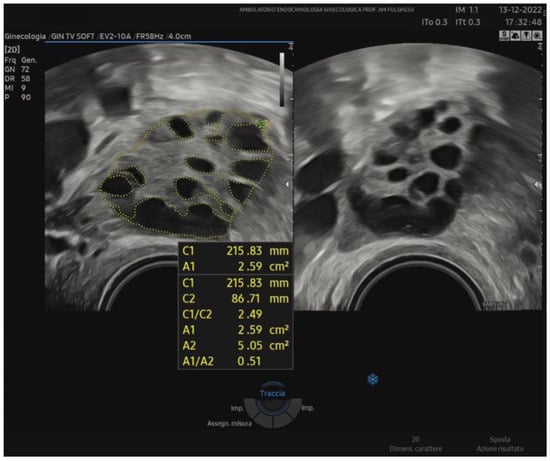

Recent investigations focus on new ultrasound markers to better characterize ovarian morphology. One method is the stromal area/ovarian area (SA/OA) ratio, which, with a cut-off of 0.32, has been proposed as a significant predictor of elevated androstenedione and testosterone levels [40]. Because the Rotterdam criteria are not recommended for adolescents due to transabdominal scans and the high prevalence of PCOM in healthy teens, some authors have suggested measuring the SA/OA ratio to reduce the risk of overdiagnosis. In studies involving normocyclic and non-hyperandrogenic adolescent girls, applying the Rotterdam guidelines (follicle count ≥ 12, OV > 10 mL) and setting the standard SA/OA ratio to ≤0.3 led to the classification of ovaries into three groups: normal morphology (NOM), PCOM with normal SA/OA (PCOM-NS), and PCOM with increased SA/OA (PCOS-IS). Notably, the prevalence of PCOM-IS remained constant across different post-menarche ages, indicating that an increased stromal ratio might be a more stable feature associated with androgen excess. Indeed, PCOM may be considered a normal and transient physiological phase in ovarian development during early adolescence, predominantly observed in the first 1–3 years post-menarche because of an immature hypothalamic-pituitary axis [41,42]. Around 1985, Adams et al. noted the characteristic peripheral arrangement of follicles around a core of hyperechoic stroma [34]. Similarly, Dewailly in 1994 observed that ovarian hypertrophy, indirectly linked to stromal hypertrophy, was easy to measure and correlated with PCOS [43]. In recent decades, numerous attempts have been made to quantify stromal echogenicity and thickness more objectively. For instance, stromal and myometrial echogenicity have been compared, considering that normal stromal echogenicity should be slightly lower than the myometrium. However, operator subjectivity and equipment differences have hindered standardization. In 2001, Fulghesu et al. [44] proposed quantifying the stromal percentage in the central zone using calipers to outline the ovarian periphery and the stromal core on a still ultrasound image corresponding to the maximum planar section of the ovary (SA/OA ratio) (Figure 1).

Figure 1.

Example of the SA/OA ratio calculation on a median ovarian section with outlined ovarian and stroma areas during a TV-US scan. A1: total stromal area; A2: ovarian area; A1/A2: SA/OA ratio (>0.32).

With this type of measurement, values of SA/OA > 0.32, which reflect a stroma occupying more than one-third of the ovary in the midsection, suggest a more pronounced androgenic profile, corresponding to a higher likelihood of PCOS. The stromal area-to-total ovary area ratio can be assessed without the need for other technologies using standard ultrasound and eliminates the problems of subjective stromal assessment encountered previously. Belosi et al. [45] confirmed that the SA/OA ratio shows minimal inter-operator variability, high diagnostic accuracy, and a strong correlation with plasma androgen levels. Moreover, by adding SA/OA ratio measurement, one can identify subgroups of patients with borderline or NIH-negative status who nonetheless display underlying hyperandrogenism. In 2007, a multicenter study in Italy corroborated these findings, demonstrating that the SA/OA ratio best predicts elevated androstenedione and testosterone levels among the various ultrasound parameters [40]. In conclusion, ultrasound-based diagnosis of PCOS still relies on the Rotterdam criteria (2003). However, adding a stromal evaluation (SA/OA ratio) may significantly improve the identification of hyperandrogenic phenotypes. Quantifying both stromal area and follicle distribution is crucial to accurately diagnosing PCOS, offering the possibility of distinguishing different phenotypes and optimizing patient management.